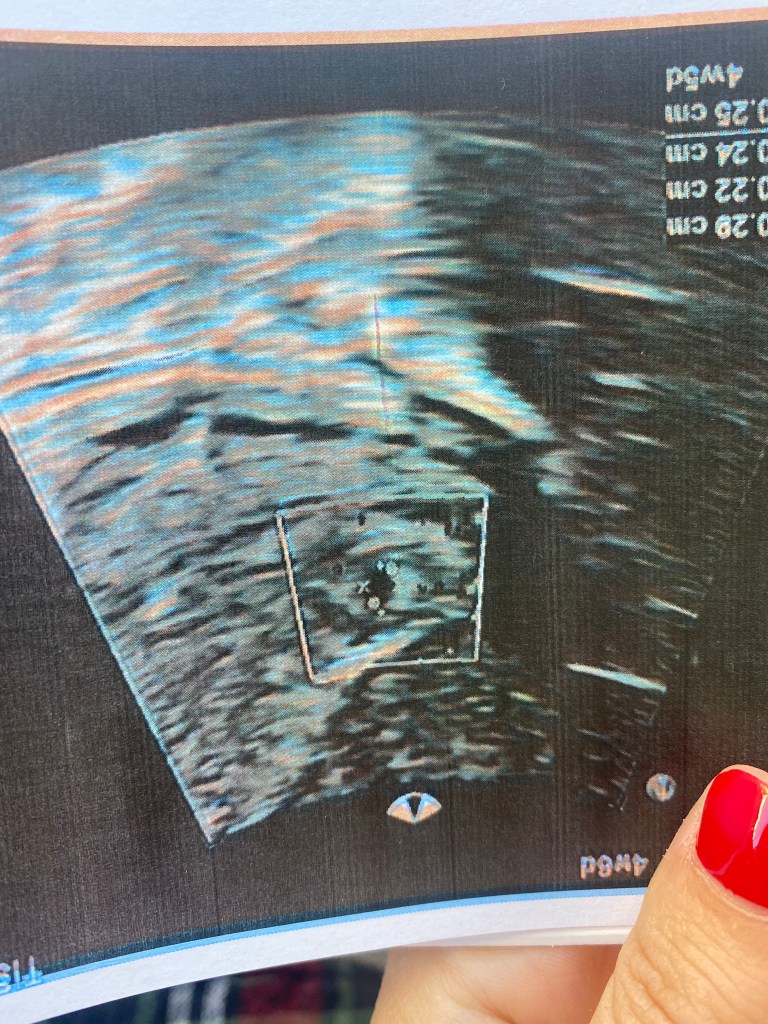

Μέσα σε όλο μου τον προγραμματισμό δεν φανταζόμουν ποτέ, επίσης, ότι θα τον ερωτευτώ. Τον ερωτεύτηκα για εκατομμύρια λόγους. Δουλέψαμε πολύ (δουλεύουμε ακόμα), περάσαμε καλά πολύ (ακόμα περνάμε), περάσαμε μία ολόκληρη καραντίνα μαζί (ίσως ξανά περάσουμε) και μέσα σε όλο αυτό το ταξίδι αποφασίσαμε να δημιουργήσουμε την δική μας οικογένεια. Σίγουρα εκτός προγράμματος ΟΛΑ! ‘Εμαθα ότι είμαι έγκυος την ημέρα των γενεθλίων μου, μπήκα στα 28 , το είχα ονειρευτεί, δεν πιστεύω στα όνειρα ή τουλάχιστον δεν πίστευα. Όσο και να το περίμενα δεν το έχω ακόμα συνειδητοποιήσει. Όλοι λένε είναι λογικό. Τα πρώτα συναισθήματα που βίωνα ήταν πολύ πολύ περίεργα, κάπως αμήχανα, ταυτόχρονα με την συνεχόμενη αδιαθεσία που ένιωθα ήταν σαν μία τεράστια έκρηξη να συνέβαινε μέσα μου. Κάθε μέρα και κάτι άλλο, κάτι νέο κάτι τελείως εκτός προγράμματος.

Είμαστε πολύ τυχεροί που θα γίνουμε γονείς σε ένα κόσμο με τόσα προβλήματα. Ανυπομονούμε να σε γνωρίσουμε Π. θα προσπαθήσουμε να σε κάνουμε έναν καλό άνθρωπο. Σε αγαπάμε ήδη!